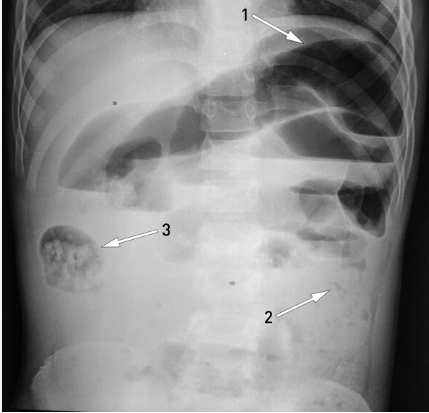

• Oclusão intestinal: Cólicas, massa periumbilical palpável, RH negativo, diarréia, eliminação oral de lombrigas